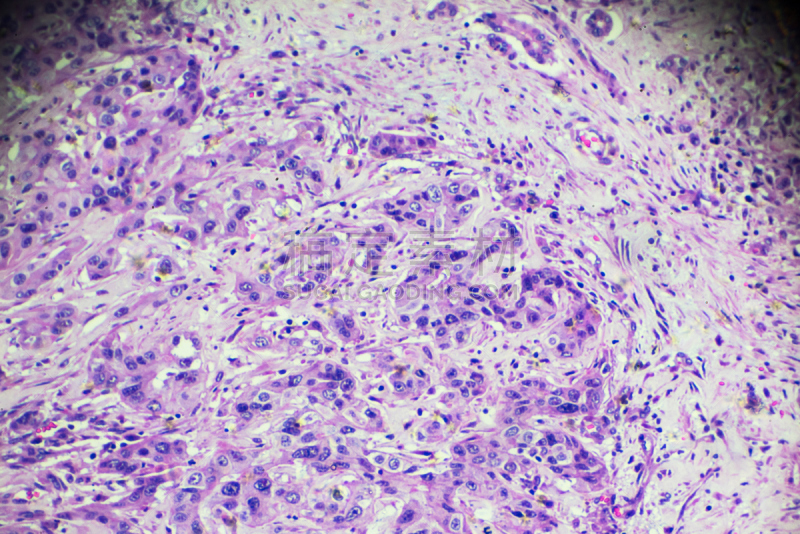

详情

JPG